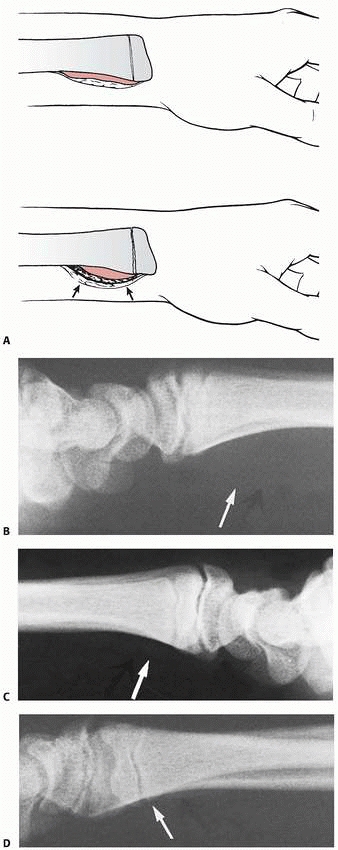

![]() |

FIGURE 9-10 A.

Subperiosteal hemorrhage from an occult fracture of the distal radius causes an anterior displacement of the normal pronator quadratus fat pad (arrows). B. A 13-year-old girl with tenderness over the distal radius after a fall. The only radiographic finding is an anterior displacement of the normal pronator quadratus fat pad (arrow). C. The opposite normal side (arrow indicates normal fat pad). D. Two weeks later, there is a small area of periosteal new bone formation (arrow) anteriorly, substantiating that bony injury has occurred. |